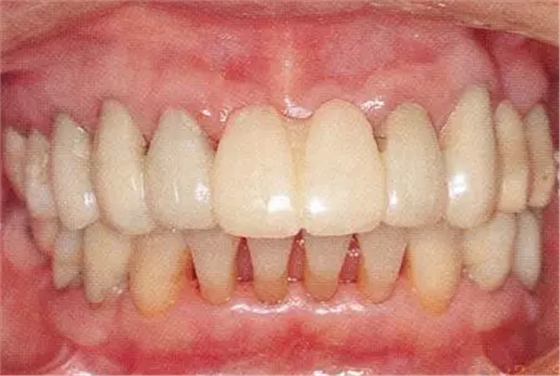

在正畸治療結(jié)束后仍然存在open contact的病例

▲圖15-1,2

在正畸??漆t(yī)生處接受了正畸治療,雖然上頜正畸治療已經(jīng)完成,但由于磨牙區(qū)的邊緣嵴不整齊而導(dǎo)致牙體之間存在空隙。要想在這個狀態(tài)下護(hù)理牙周組織以及咬合狀況是非常困難的。由此可見,在治療時,正畸??漆t(yī)生與全科口腔醫(yī)生保持目標(biāo)一致是非常重要的。